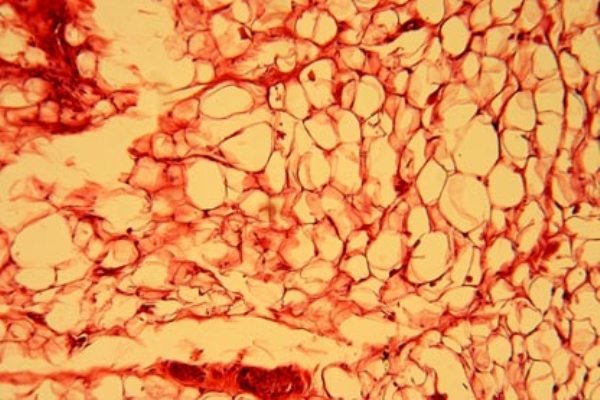

نوع غیرسالم چربی که با دیابت و اضافه وزن در ارتباط است تحت عنوان «چربی سفید» شناخته می شود که ترکیبی از بافت های بزرگ سلولی دربرگیرنده مقادیر هنگفتی انرژی است. اما چربی های «خوب» نیز وجود دارند.

آنچه که تحت عنوان چربی خوب از آن یاد می شود، بافت چربی قهوه ای رنگی است – سلولهایی که کوچکتر هستند و میتوکندری موجود در آنها چربی را سریعا به انرژی تبدیل می کند.

اساسا چربی قهوه ای تحت عنوان «چربی کودک» شناخته می شود که در حیواناتی که خواب زمستانی دارند نیز یافت می شود. محققان پیشتر متوجه شده اند که افراد بزرگسال دارای چربی قهوه ای هستند اما از این نکته مطمئن نبوده اند که چربی قهوه ای یا همان چربی کودک در واقع همان چربی است که همزمان با تولد نوزاد در بدنش وجود دارد.